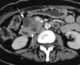

Invasive neoplasm

A neoplasm () is a type of abnormal and excessive growth, called neoplasia, of tissue. The growth of a neoplasm is uncoordinated with that of the normal surrounding tissue, and persists in growing abnormally, even if the original trigger is removed. [Source: Wikipedia ]